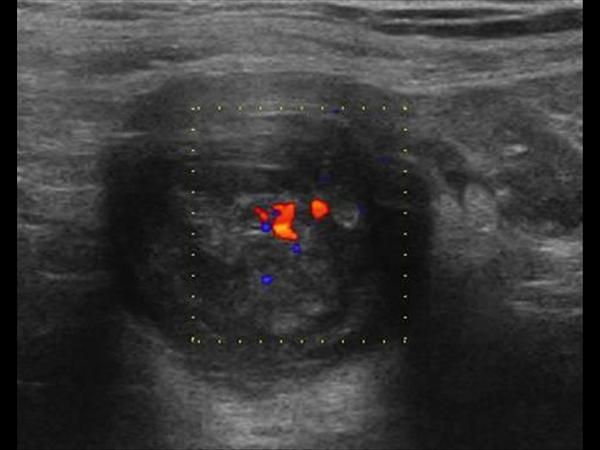

Mucocele ruột thừa

» Thông tin: Nam giới – 71 tuổi.

» Lâm sàng: Đau hố chậu phải mạn tính.